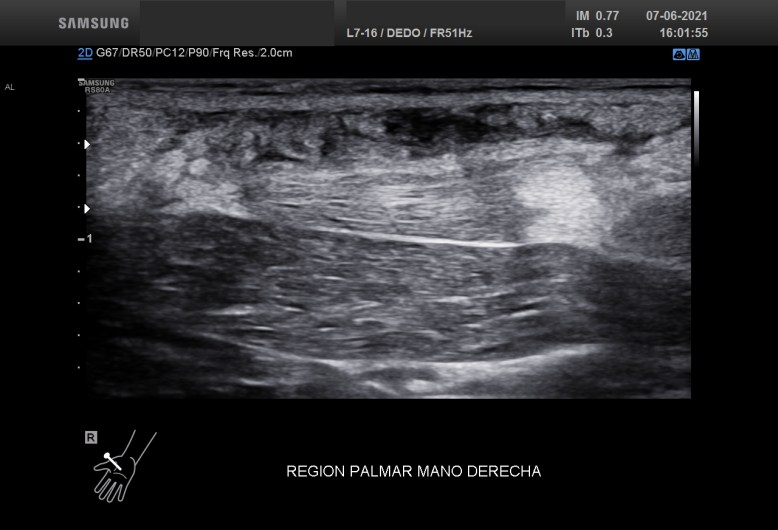

La imagen 5 y 6 te la pongo para que puedas ver como es el tejido afecto con el tejido conservado normal. Son Comparativos. Como la ecoestructura normal del TCS está respetado e integro. La musculatura y los vasos comparados y documentados con sus respectivos pictogramas.

Finalmente, el doppler para demostrar vascularizaciones anómalas que este caso no existían o no pudieron ser demostradas con la técnica habitual.